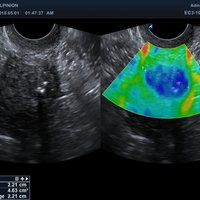

• Elastographie, Panoramic Imaging, Needle Vision (Nadelvisualisierung), Needle Vision Plus (Spezialfunktionen)